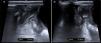

Varón de 3 años con 72h de dolor abdominal intermitente, fiebre de 3h y vómitos autolimitados; asociaba episodios de llanto, encogimiento de piernas y diaforesis. El abdomen era difusamente doloroso y difícilmente valorable. La ecografía tuvo escasa rentabilidad por poca cooperación, sin identificar el apéndice ni signos inflamatorios. La analítica mostró leucocitosis (20.500/mm3), PCT 0,5ng/ml y PCR 61mg/l. Ante el dolor abdominal de etiología no filiada, y sin poder descartar una causa quirúrgica, ingresó en observación. Por persistencia sintomática se repitió la analítica 14h después identificando menos leucocitosis (19.100), descenso de PCT (0,3), aunque ligera elevación de PCR (69). Una nueva ecografía mostró un apéndice de hasta 11mm (fig. 1) y la cirugía reveló un plastrón no purulento conteniendo un apéndice torsionado que fue resecado. Los hallazgos operatorios se muestran en la figura 2 y se ilustran en la figura 3. La evolución postoperatoria fue favorable, dándose el alta 5 días después.